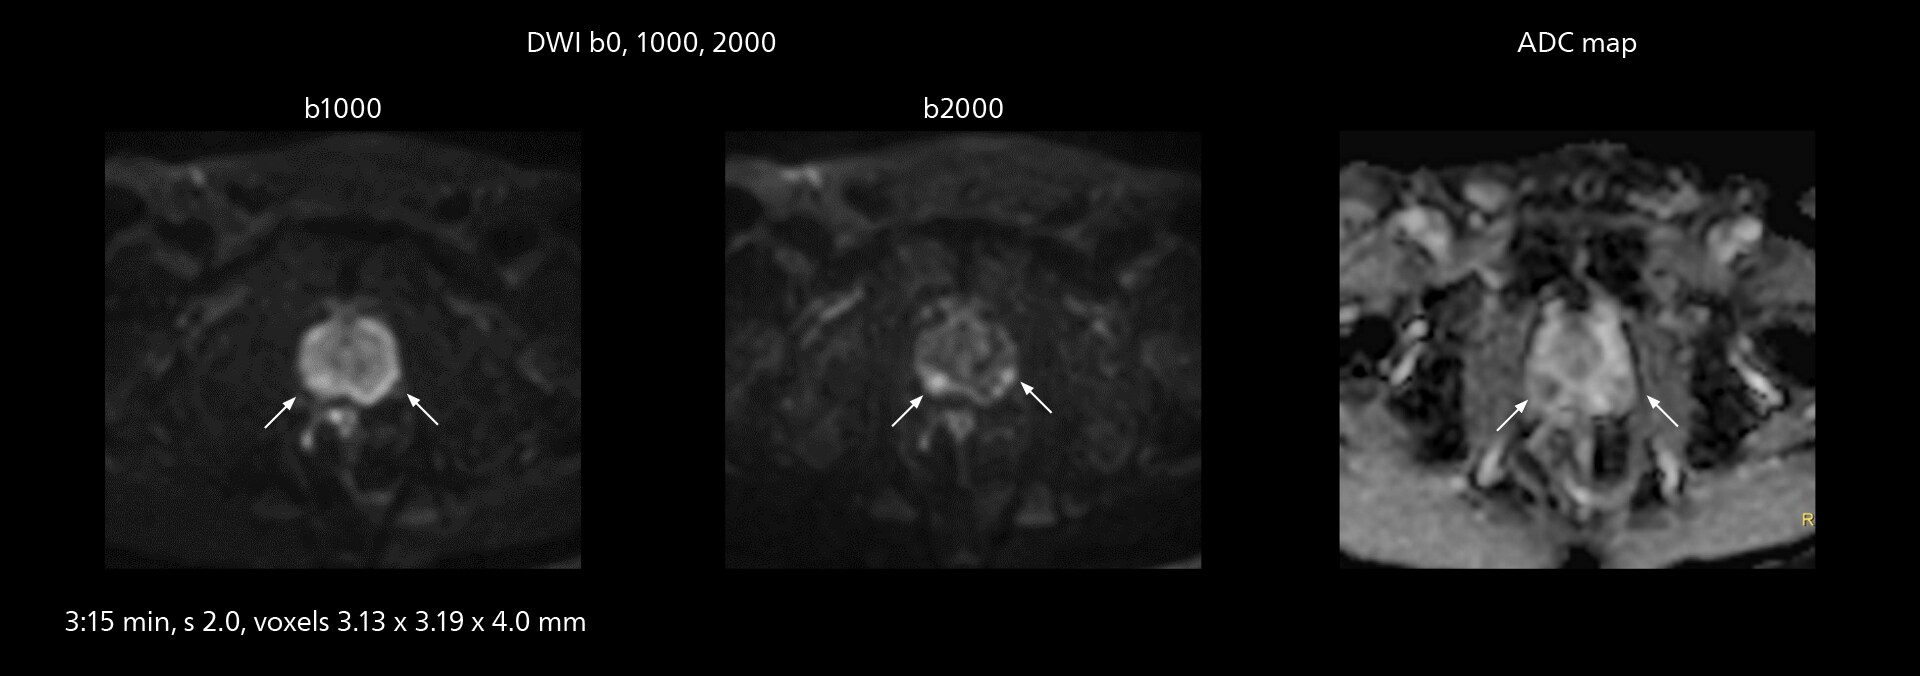

The high performance of the Vega HP gradients is particularly impressive in DWI. “The Vega HP gradients enable us to scan faster and use b-values as high as 2000, for example in prostate DWI and in DWIBS, which provides image quality that is remarkably improved over the previous system and we are able to more easily see lesions.”

The value of the Elition X gradients is also evident in DWIBS studies. “The fact that we can consistently obtain distortion‐free DWIBS while reducing imaging time at three coronal stations is excellent,” Dr. Makuuchi says. “In these patients, it’s also important that the application of Compressed SENSE to T2‐weighted, STIR and mDIXON sequences has no impact on the examination time of whole‐body imaging. As a result of the increased speed and higher image quality we realize, DWIBS studies have now become routine examinations.”

With SmartPath to Elition X the team can obtain excellent quality DWIBS imaging and reduce imaging time. Other sequences also fit in the examination slot. This case shows left paravertebral neurogenic tumor and Th10 vertebral hemangiomas.